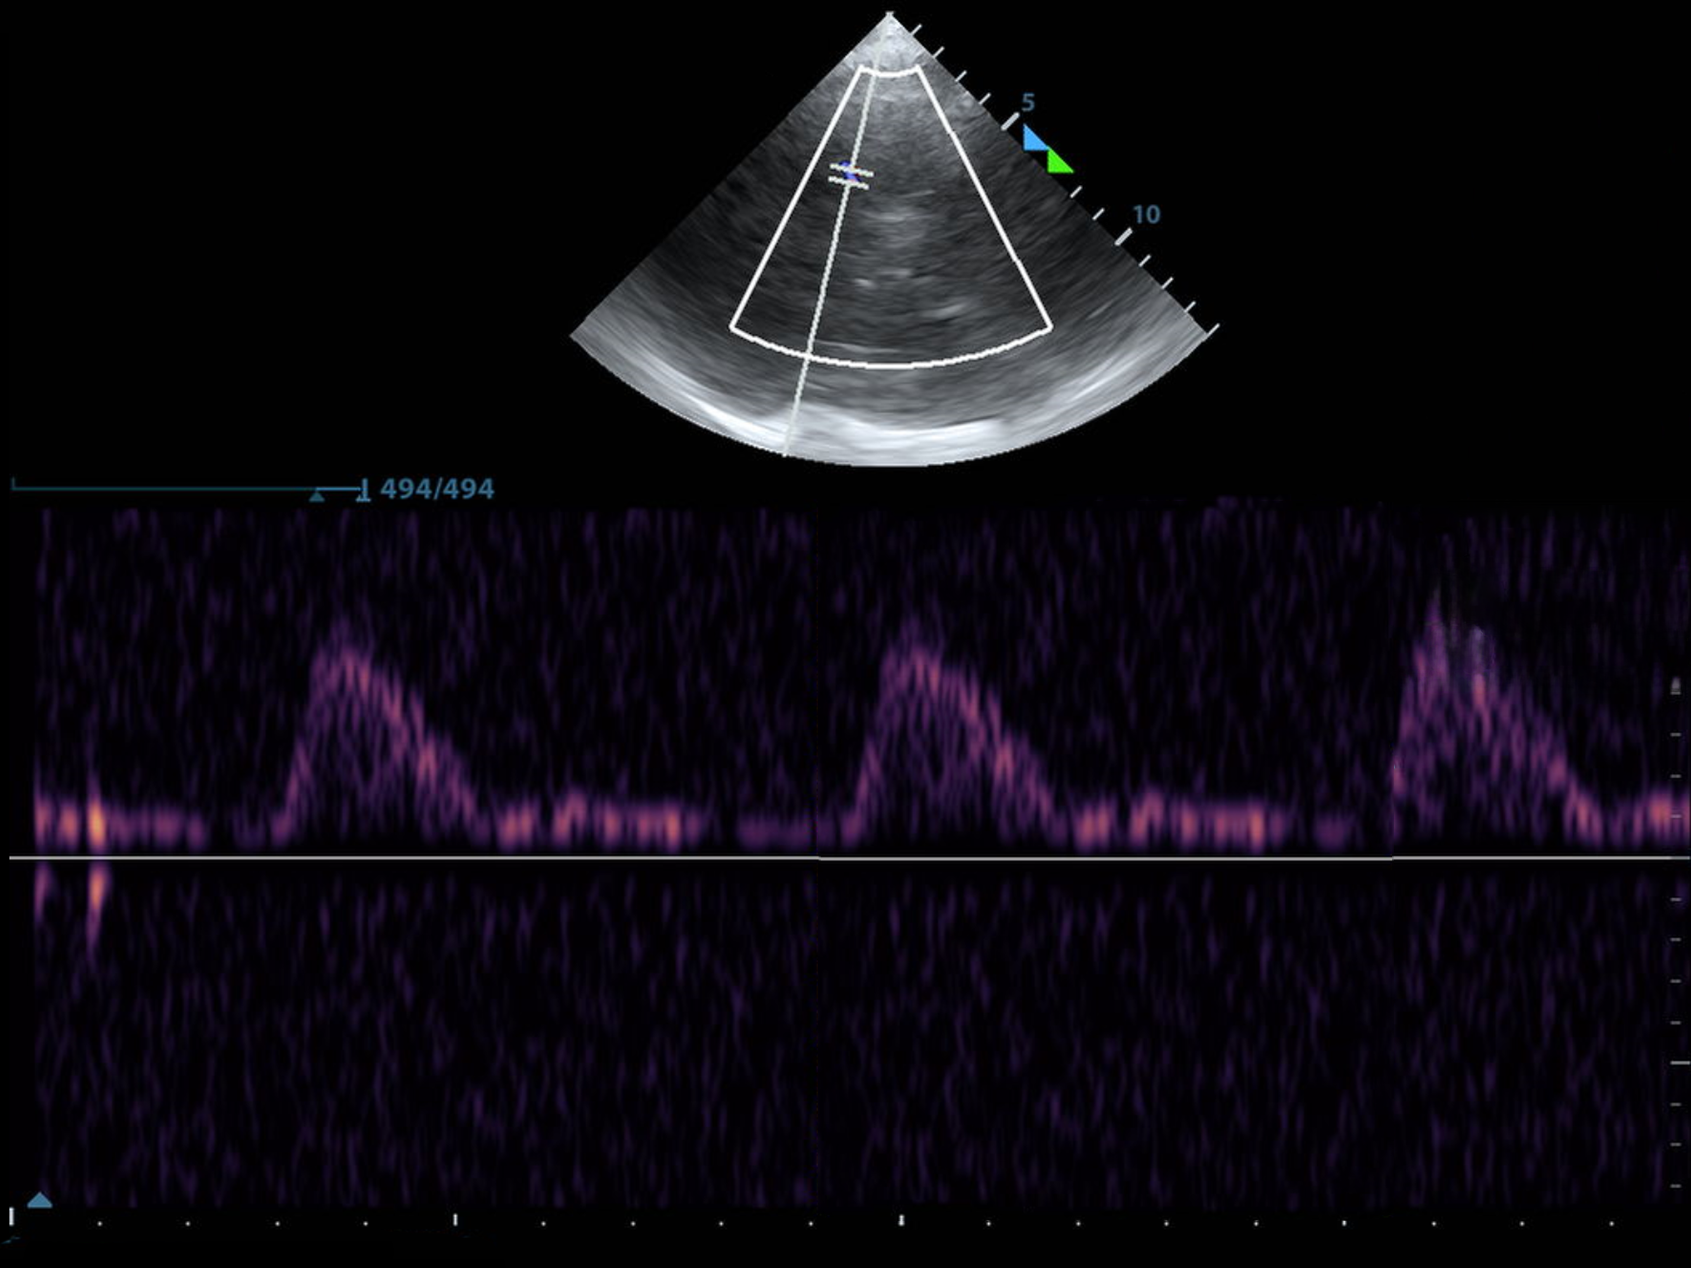

Making Waves: Adding Spectral Doppler

Elevated Intracranial Pressure